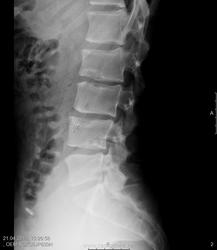

При общей оценке боковой сподилограммы обращают на себя внимание "пляшущие" позвонки, при чем каждый из них- сам по себе. Я бы сказал: "кто в лес, кто по дрова". Для примера снимки в 32, 53, 73 года и 60 лет. Здесь если и есть патология, то "пляшущих" позвонков точно нет:

Какого Шморля?) Центрального. Консолидированный перелом L2, а может и L4, судя по увеличению передне-заднего размера, сглаженность лордоза с посттравматическим кифозом. Или буйная фантазия)). А на счет травм в анамнезе - про свой перелом узнала, став рентгенологом)). Чаще мы не помним про детские травмы. Ну или +склероз))).